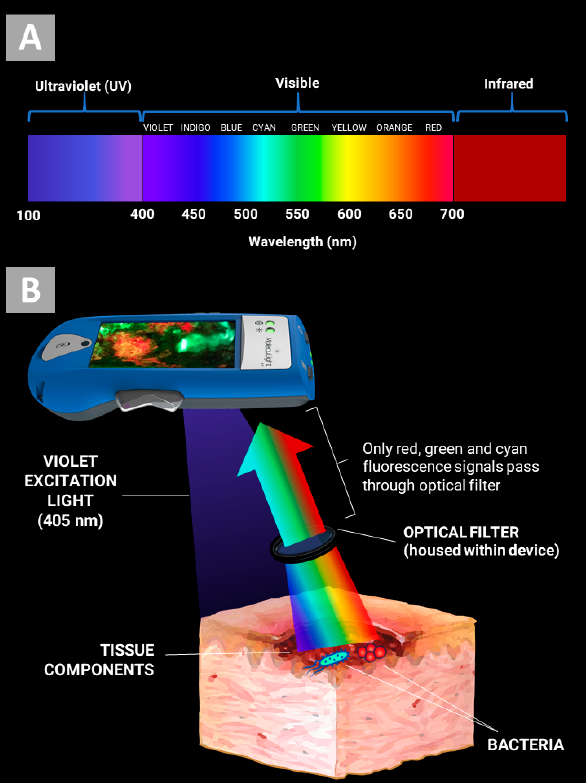

Understanding Real-Time Fluorescence Signals from Bacteria and Wound Tissues Observed with the MolecuLight i:X

Rennie, MY et al. Diagnostics 2023

In vitro detection of porphyrin-producing wound bacteria with real-time fluorescence imaging

Jones, LM et al. Future Microbiol 2020

Detection of bacterial fluorescence from in vivo wound biofilms using a point-of-care fluorescence imaging device

Lopez, AJ et al. Int Wound J 2021